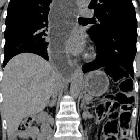

CT

Patients with uncomplicated achalasia demonstrate a dilated, thin-walled esophagus filled with fluid/food debris.

Overall, CT has little role in directly assessing patients with achalasia, but is useful in assessing common complications. Careful assessment of the wall of the esophagus should be undertaken to identify any focal regions of thickening which may indicate malignancy. The lungs should be inspected for evidence of aspiration.